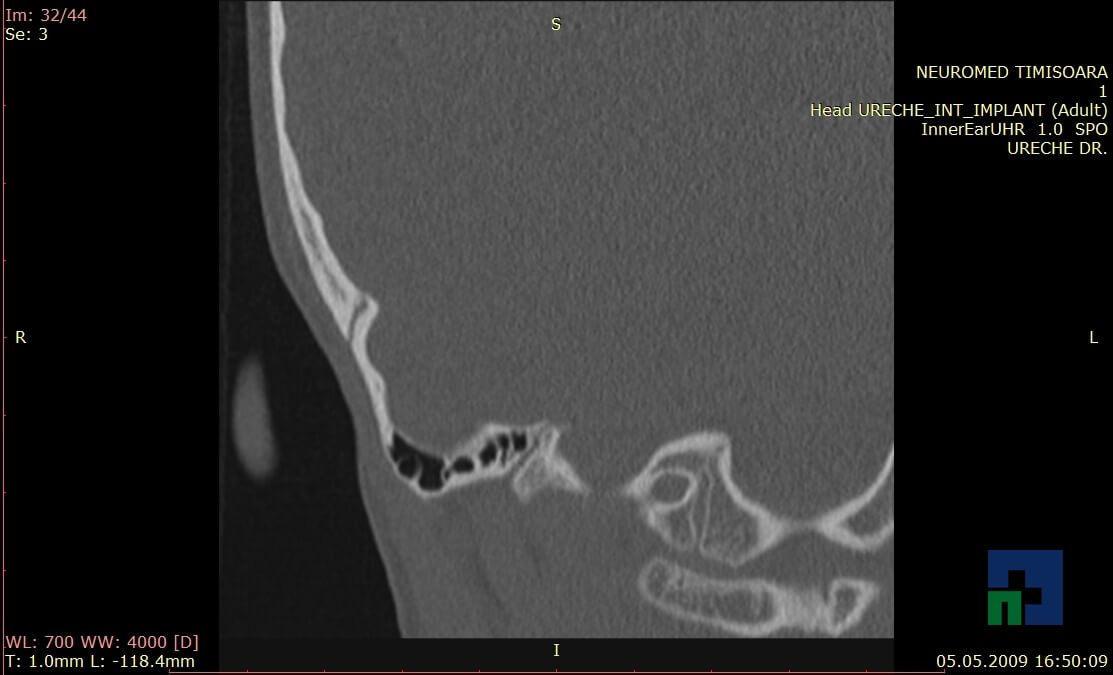

- Diagnosticul traumatismelor de bază de craniu

- Diagnosticul fracturilor:

-

- Unice

- Multiple

- Cu înfundare

- Complexe cranio-sinusale

- Complexe cranio-etmoidale

- Complexe cranio-orbitare

- Complexe cranio-faciale